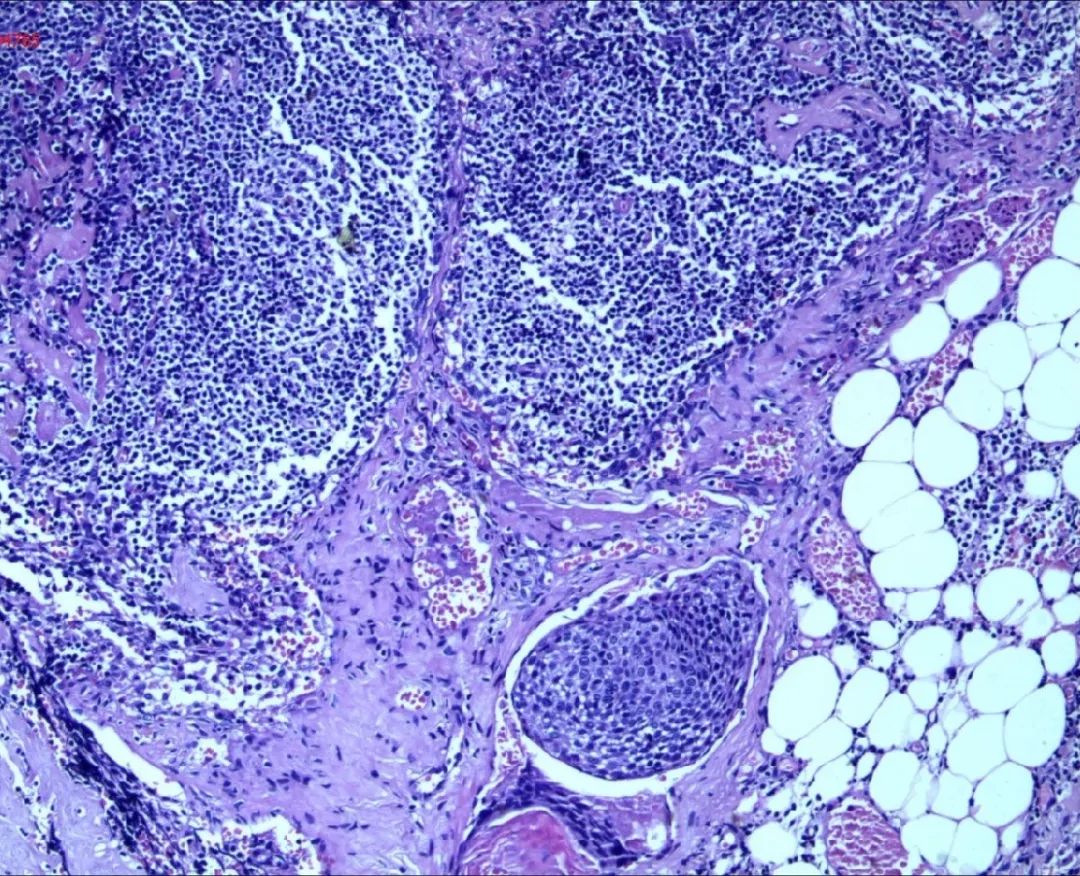

通过盆腔MRI发现子宫颈-子宫体中下段占位,考虑诊断宫颈癌

宫颈活检病理显示刘女士患有非角化型鳞状细胞癌